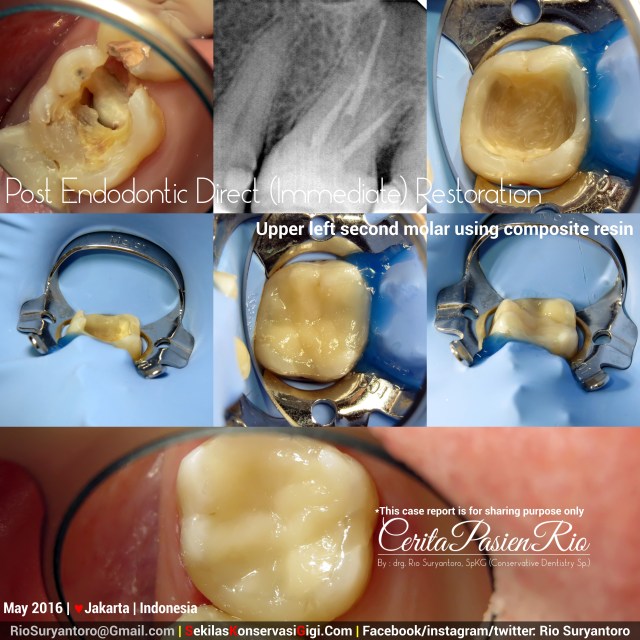

Post Endodontic Direct (Immediate) Restoration

This is the restorative procedure which i’ve done in my patient after root canal procedure on my previous case of endodontic treatment of upper left first molar with remaining buccal and palatal wall. (Refer to case 68 in SekilasKonservasiGigi.Com)

n order to make a difference in working appearance, i changed the rubberdam clamp from Hu-Friedy to SanctuaryRubberdam but still using NictoneRubberdam sheet.

This tooth deserve a crown/onlay/endocrown for its definitive restoration, but as intermediate restoration i did it with composite resin. After taking proper informed consent, i place the packable composite (Estelite from Tokuyama) shade A2 without tin or color modifier. Polished it with Soflex (3M) and Enhance (Dentsply).